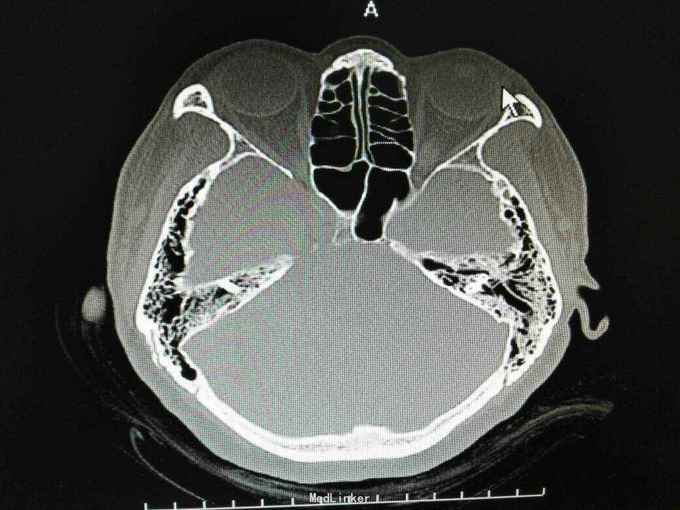

外耳道胆脂瘤,并 分泌性中耳炎? 胆固醇肉芽肿?

患者女性,47岁,以听力下降一周为主诉入院。 就诊后见外耳道后壁缺损,鼓室內积液,给予抗炎治疗后,鼓室內积液由缺损外耳道排出,呈棕褐色。 辅助检查:纯音听阈基本无听力损失。 诊断 外耳道胆脂瘤,并 分泌性中耳炎? 胆固醇肉芽肿? 治疗: 1.乳突根治术?乳突蜂房气化非常好,比较难做。 2.外耳道成型、后壁修补?